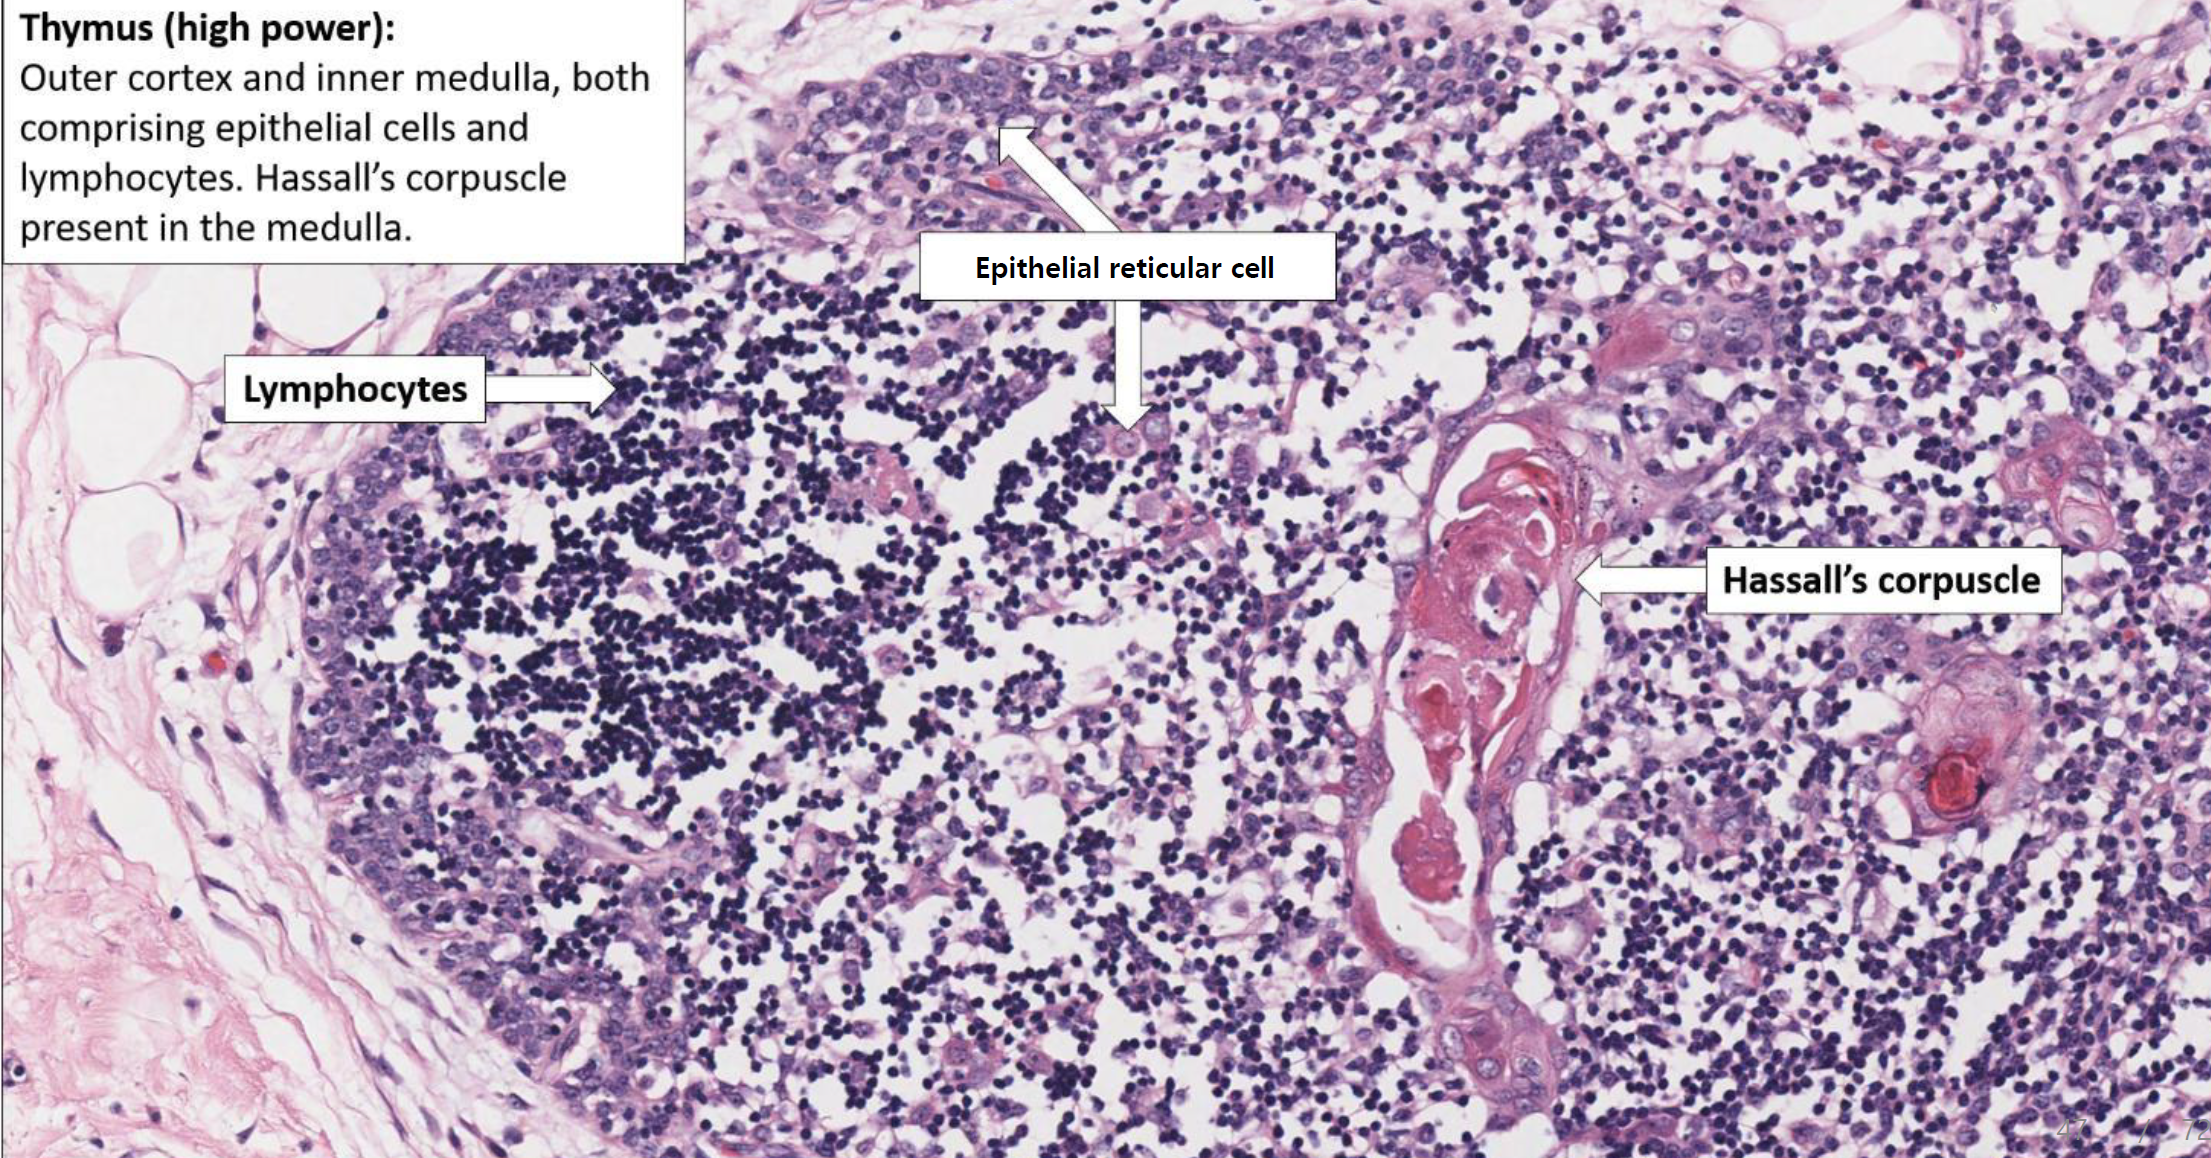

가슴샘

- reticular cell과 그것이 회오리치는 thymic corpuscle(hassall's corpuscle)을 가진다.

- cortex와 medulla로 구성된 lobule은 septum로 구분되고, 전체를 capsule이 감싼다.

- T cell은 cortex에서 medulla 방향으로 이동한다. 이때 epithelial reticular cell과 desmosome이 검문을 수행한다.